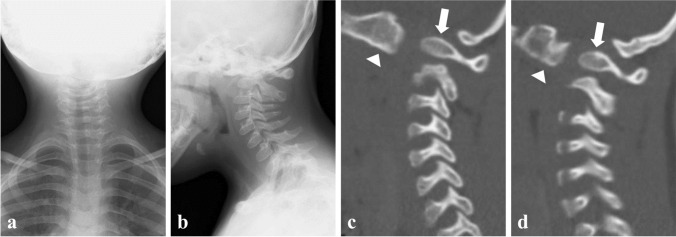

The patient first presented to our department at 3 years of age for abnormal cervical radiography findings. He was diagnosed with Down syndrome at birth. His family history was unremarkable. Radiography showed basilar invagination and kyphotic O-C2 alignment (Fig. 1a, b). Sagittal reconstruction computed tomography demonstrated that the bilateral occipital condyles were anteriorly displaced to the C1 lateral masses, forming vertical O-C1 joints (Fig. 1c, d). He had no history of trauma; therefore, this condition was diagnosed as congenital atlanto-occipital dislocation. We started an annual outpatient clinic follow-up because he showed no signs of myelopathy. At 13 years of age, the patient presented with progressive gait disturbance and difficulty sitting due to cervical myelopathy. Cervical radiography revealed a mobile atlantoaxial segment with basilar invagination and O-C2 kyphosis (Fig. 2a–c). Computed tomography revealed os odontoideum protruding into the foramen magnum with bilateral atlanto-occipital dislocation (Fig. 2d–f). Magnetic resonance imaging showed kyphotic alignment of the spinal cord with severe compression at the foramen magnum level (Fig. 2g).

Fig. 1.

Cervical spine images at 3 years old. a, b Anterior–posterior and lateral plain radiographs of the cervical spine at 3 years old. c, d Reconstructed parasagittal computed tomography of the cervical spine at 3 years old revealing anteriorly displaced right (c) and left (d) occipital condyles (white arrow heads) to the C1 lateral masses (white arrows)